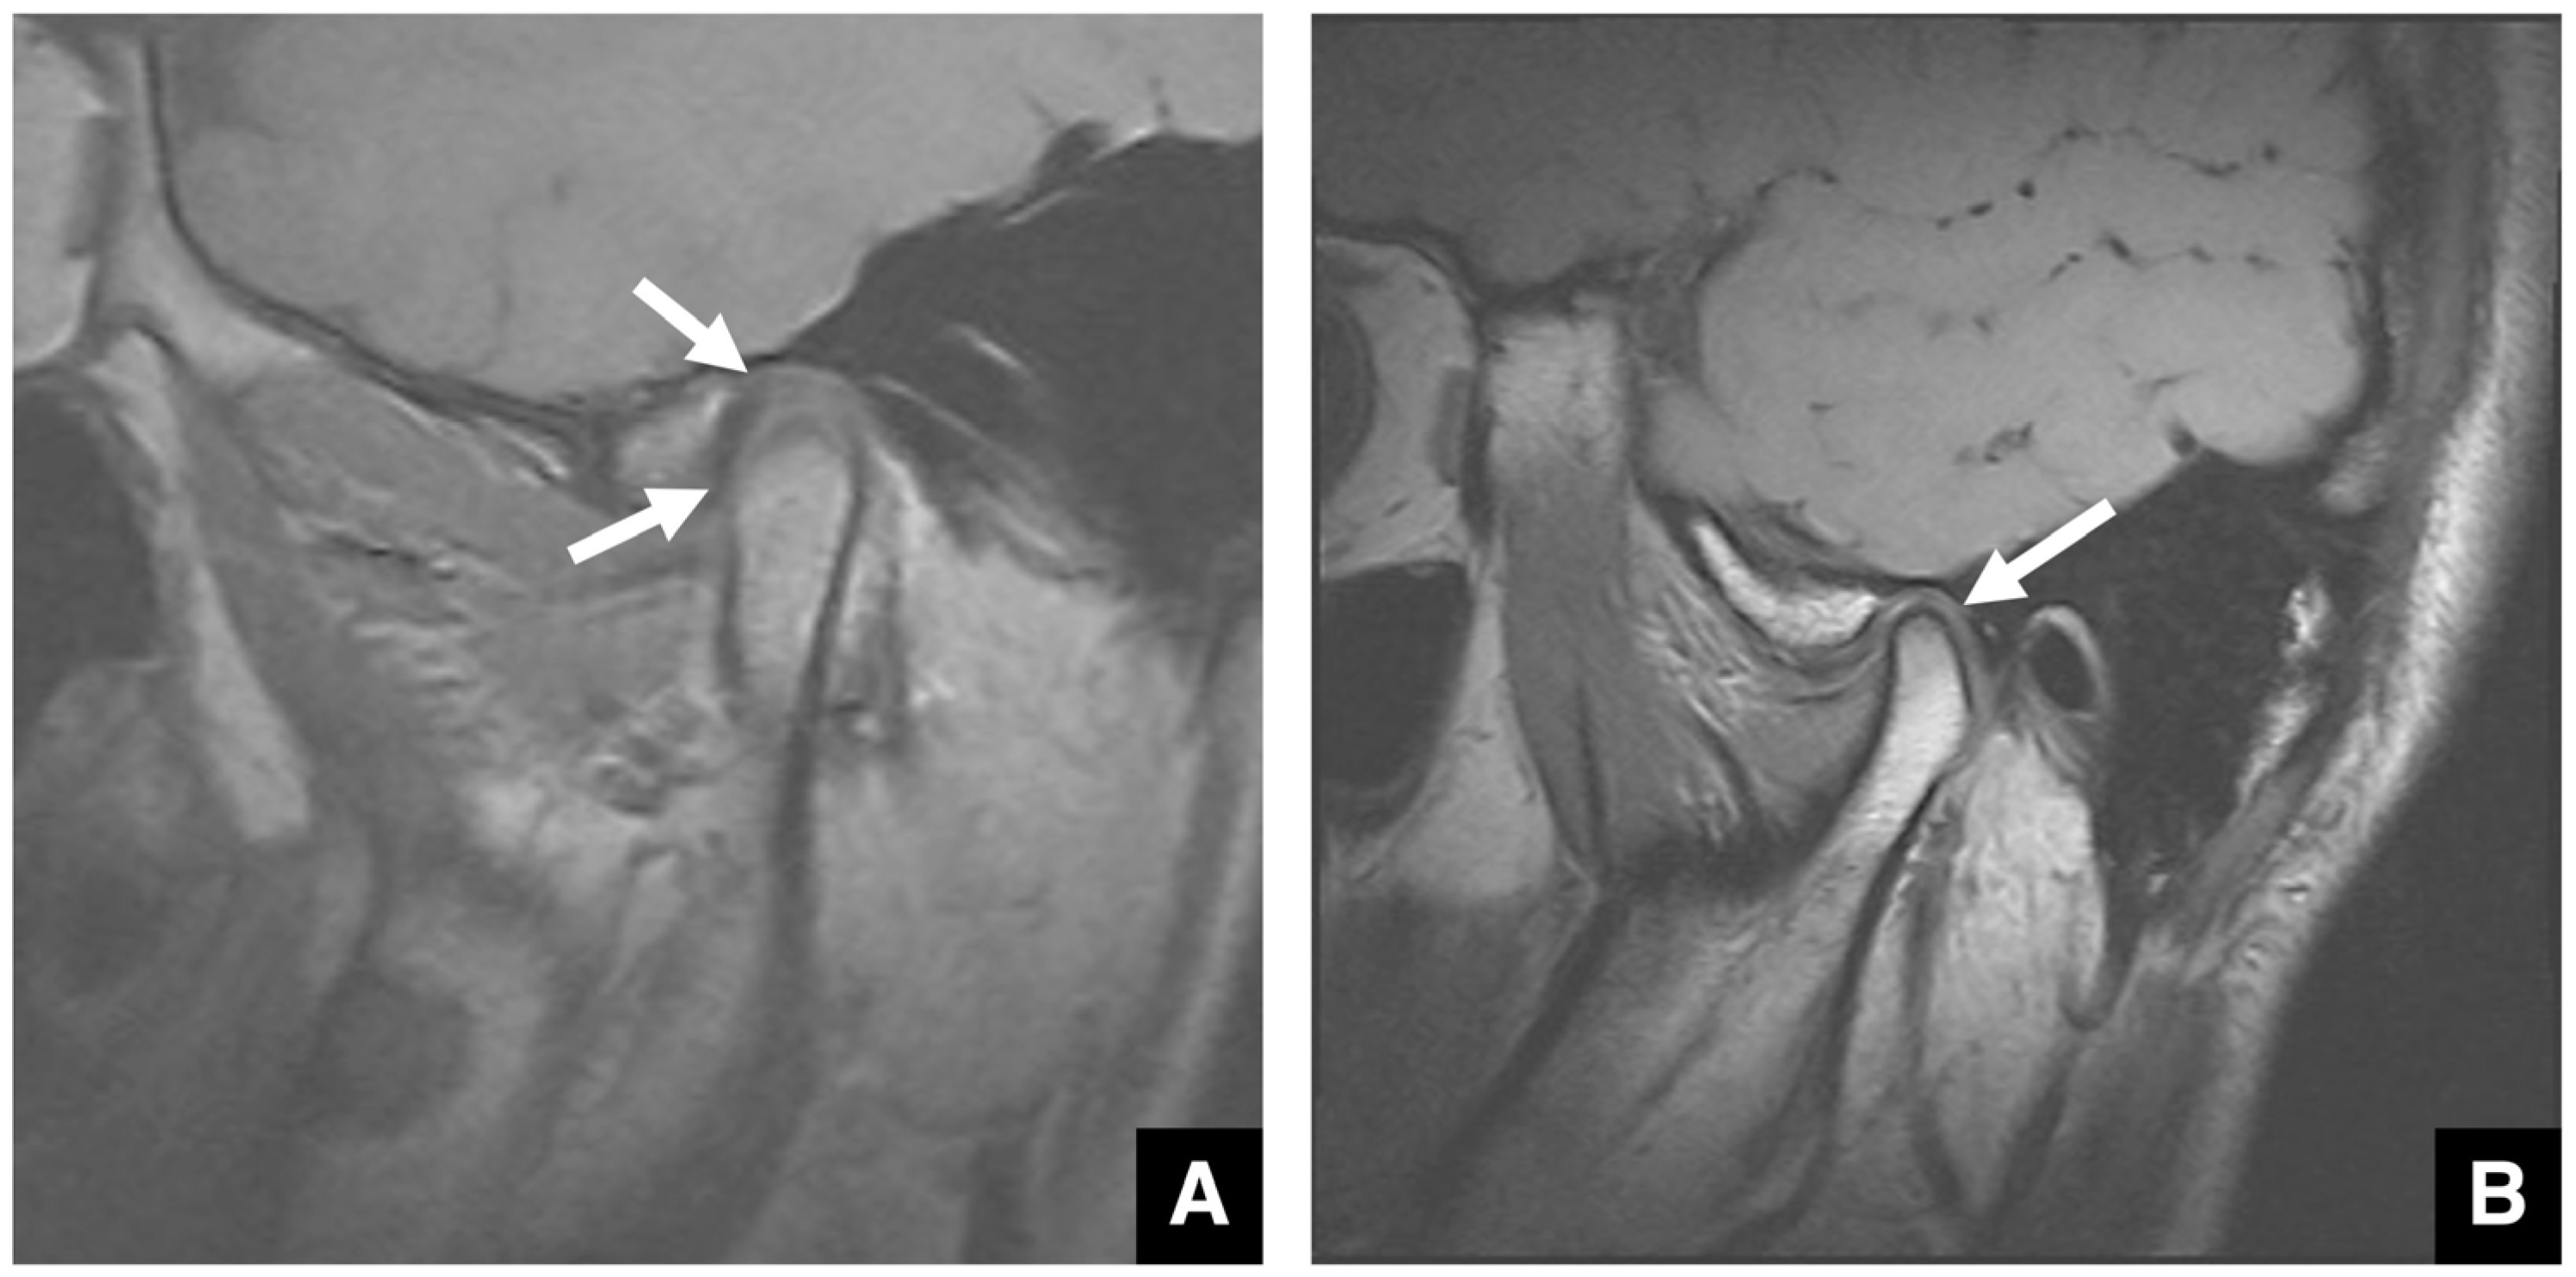

2.6. Imaging Evaluation of the TMJ in Jaw Deformities

- Ünsal, G.; Orhan, K.; Tamimi, D. Imaging of the Temporomandibular Joint Interventions. Neuroimaging Clin. N. Am. 2025, 35, 539–552. [Google Scholar] [CrossRef]

- Riechmann, M.; Schmidt, C.; Ahlers, M.O.; Feurer, I.; Kleinheinz, J.; Kolk, A.; Pautke, C.; Schön, A.; Teschke, M.; Toferer, A.; et al. Controversial Aspects of Diagnostics and Therapy of Idiopathic Condylar Resorption: An Analysis of Evidence- and Consensus-Based Recommendations Based on an Interdisciplinary Guideline Project. J. Clin. Med. 2023, 12, 4946. [Google Scholar] [CrossRef]

- Nunes de Lima, V.; Faverani, L.P.; Santiago, J.F., Jr.; Palmieri, C., Jr.; Magro Filho, O.; Pellizzer, E.P. Evaluation of condylar resorption rates after orthognathic surgery in class II and III dentofacial deformities: A systematic review. J. Craniomaxillofac. Surg. 2018, 46, 668–673. [Google Scholar] [CrossRef] [PubMed]